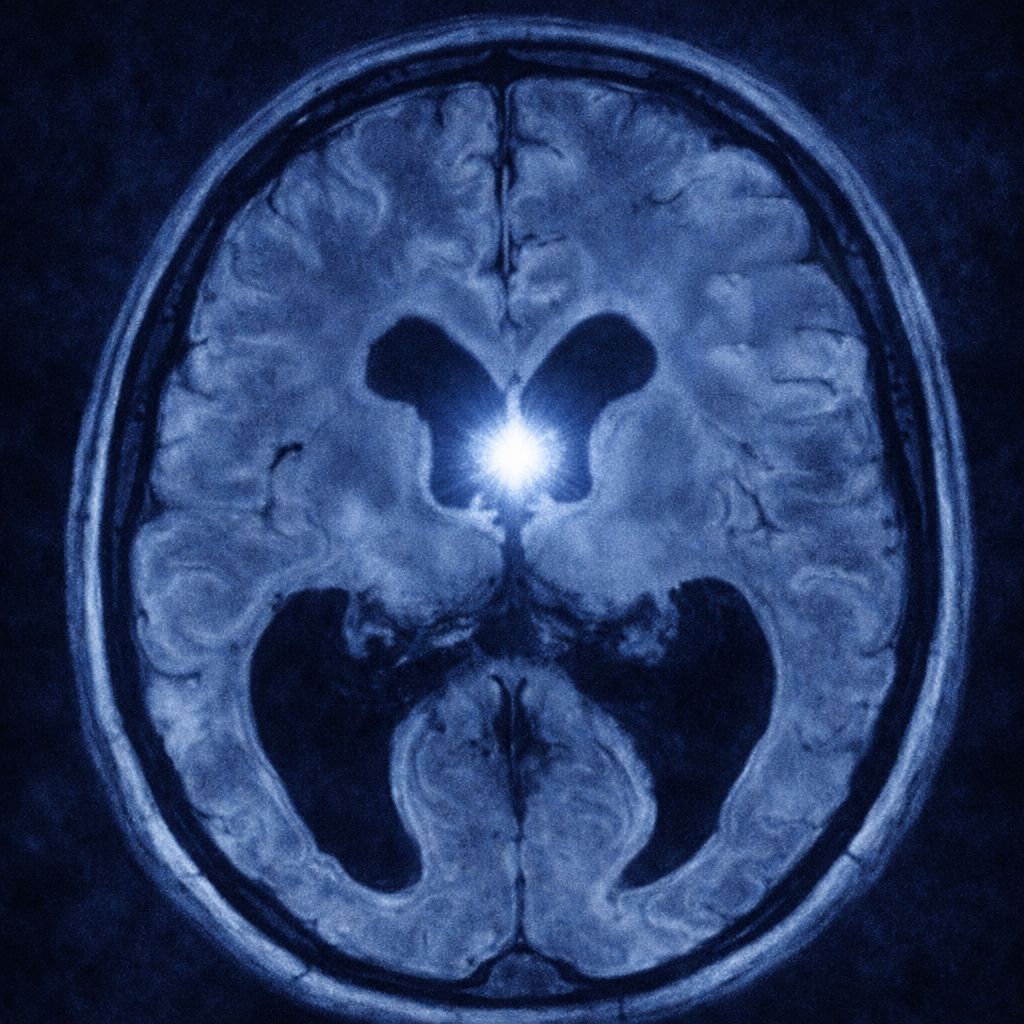

Quiste coloide

El quiste coloide es una lesión benigna que se forma en el cerebro, específicamente en el tercer ventrículo, una cavidad que contiene líquido cefalorraquídeo (LCR). Está compuesto por una cápsula fina que rodea un material gelatinoso llamado coloide. Aunque es una condición poco frecuente, puede causar síntomas graves si bloquea el flujo normal del LCR, lo que provoca hidrocefalia y aumento de la presión intracraneal. En la mayoría de los casos, el quiste coloide se detecta en adultos jóvenes y suele crecer lentamente.

El diagnóstico se realiza mediante estudios de imagen:

- Resonancia magnética (RM): permite visualizar el tamaño, ubicación y características del quiste.

- Tomografía computarizada (TC): útil para evaluar la densidad y descartar otras lesiones. En algunos casos, se complementa con pruebas neurológicas para valorar el impacto en la función cerebral.